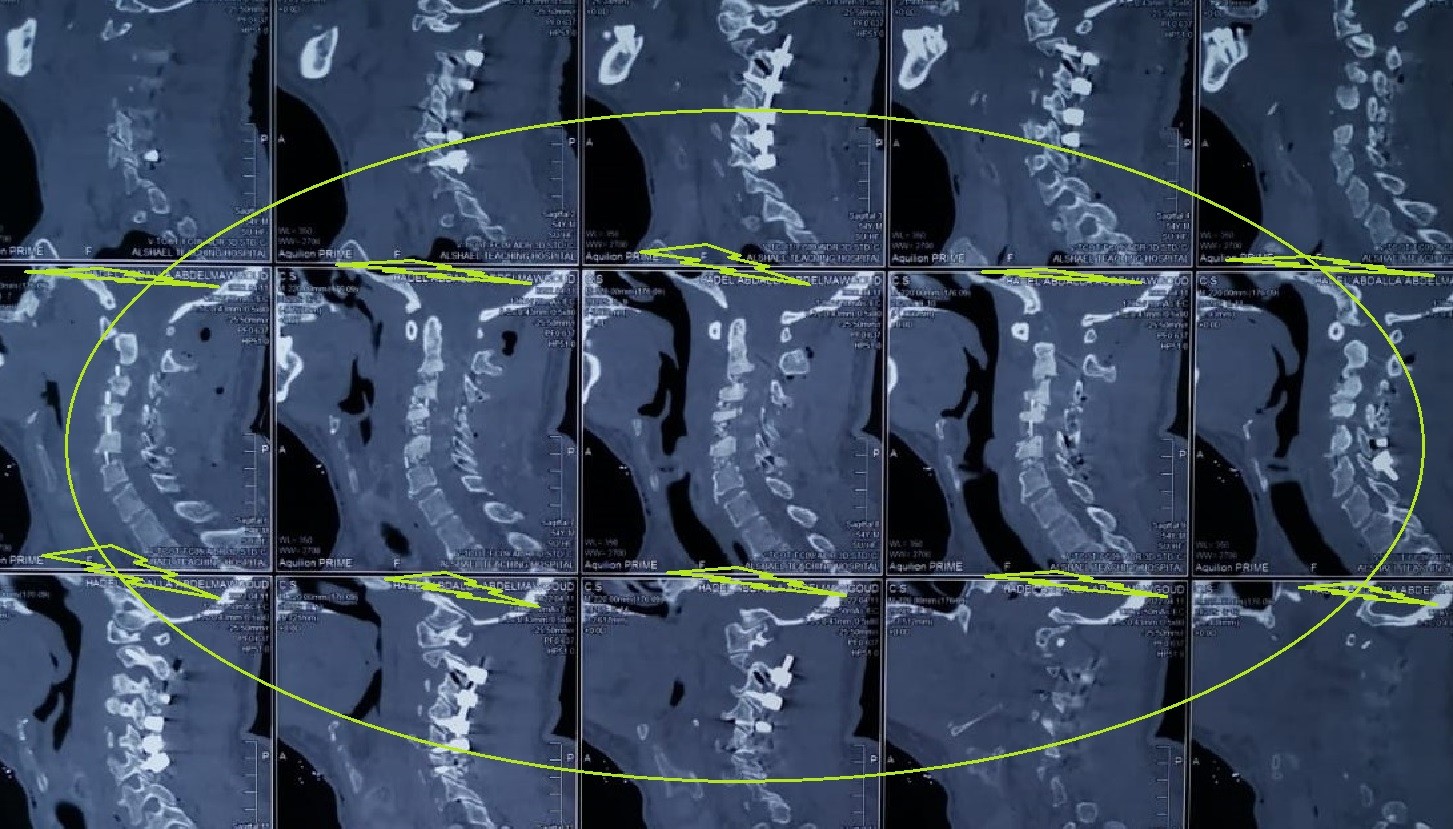

cervical vertebrae kyphosis repair